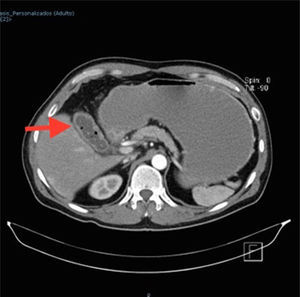

A 57-year-old man with an unremarkable past medical history complained of moderately intense localized pain in the epigastrium after eating solid foods, and later after drinking liquids. The accompanying nausea and vomiting caused important fluid and electrolyte imbalance, for which he was hospitalized. Laboratory tests and imaging studies were ordered and chronic cholecystitis with gallstones was diagnosed through ultrasound imaging (USG). A lesion infiltrating into the first portion of the duodenum and an ulcer were identified at endoscopy and at esophagogastroduodenography (EGD) (fig. 1). A computed axial tomography scan showed gas in the gallbladder and thickening of the gastric antrum and the duodenal bulb walls (figs. 2 and 3). Tumor markers were in the normal range. The patient underwent exploratory laparotomy that revealed chronic inflammation of the gall bladder, cholecystoduodenal fistula with loss of the normal anatomic arrangement, and annular pancreas (figs. 4 and 5) that did not compromise the integrity or permeability of the duodenum. Cholecystectomy was performed, the fistula was dismantled, and primary closure of the duodenum was carried out. The patient progressed favorably and is currently under follow-up at the hepatopancreaticobiliary surgery clinic.